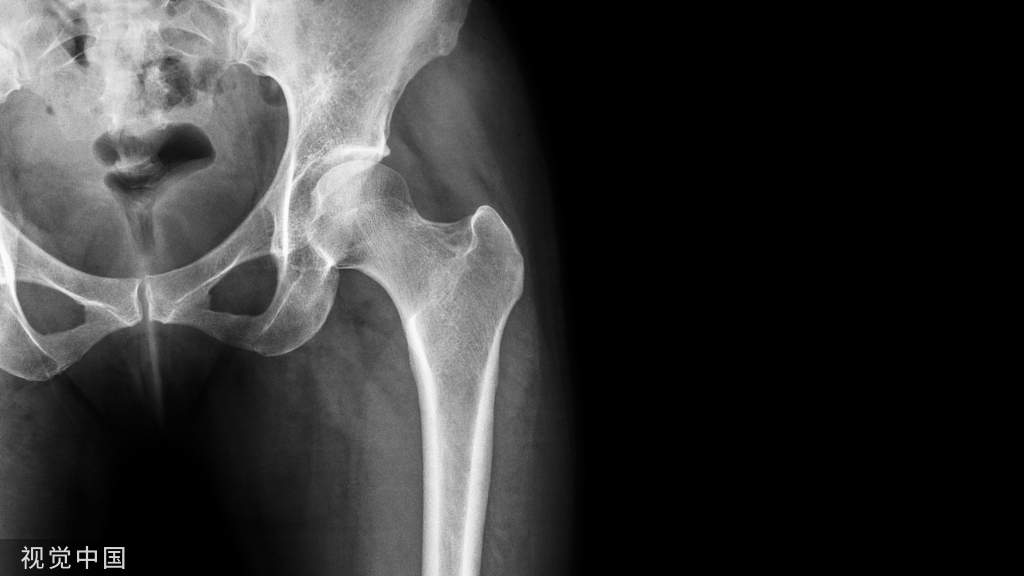

股骨颈骨折的medial buttress

垂直型股骨颈骨折(Pauwels III型)常因垂直剪力大、常规三枚平行空心钉固定易致内固定失败,单纯空心钉+第四枚垂直螺钉或medial buttress 钢板可起到对抗垂直剪力的防滑、支撑作用。

股骨颈内侧的防滑、支撑(Medial buttress)

Medial buttress是指在股骨颈骨折解剖复位、平行拉力钉常规加压后,于股骨颈下内侧、放置一块3-4孔三分之一管型钢板、重建钢板或其它微型钢板,在紧靠骨折尖下方打入一枚穿过双层皮质的防滑螺钉(Buttress screw),再在远、近侧根据情况打入第二枚或更多螺钉。这样,通过钢板的支撑作用可将骨折断端间的垂直剪切力转化为利于骨折愈合的压应力。这种应力转化有利于预防垂直型不稳定股骨颈骨折常见的内翻塌陷及不愈合并发症[Mir 2015]。